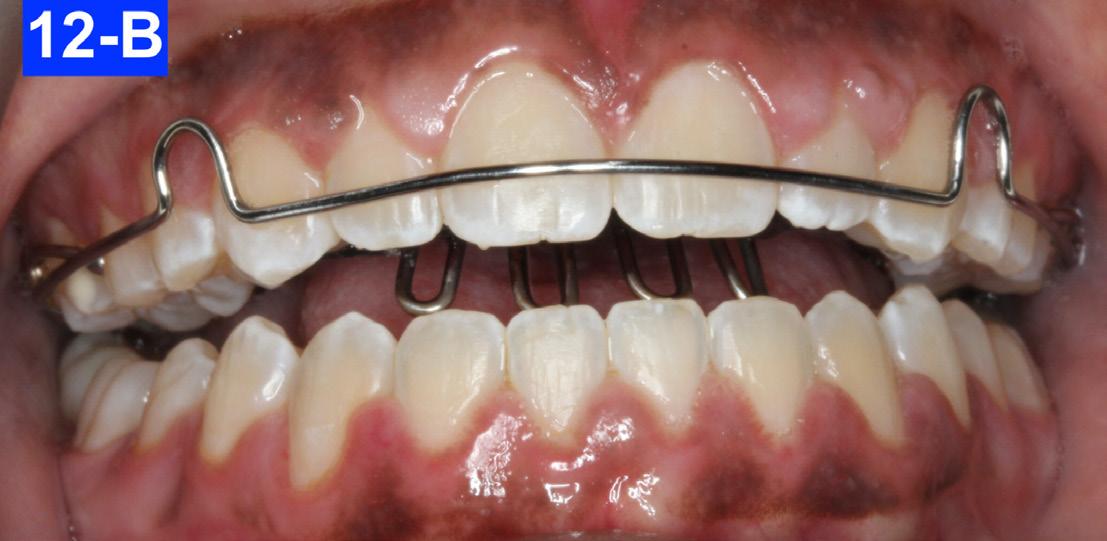

Retention and Post-Treatment Follow-up

The retainers comprised of a maxillary wraparound modified Hawley retainer with a crib and a spinner. Also, bonded retainers from #43(27) to #33(22) and from #13(9) to #23(11) were inserted. The bonded retainers were made of a .0215 SS flexible spiral (braided) wire, and bonded with Unitec Bond 1, and Tetric Evo (Ivoclar). The patient was instructed to wear her Hawley retainer 24/7 (except sports, brushing her teeth and meals) for 12 months, and after this, only at night. The bonded retainers were recommended to stay indefinitely. The prescribed OMT were reviewed and the benefits of continually practising them reinforced.

Figures 12-A to 12-M show the post-treatment images at the time of insertion of the retainers. We had an opportunity to evaluate the patient’s occlusion three years post-treatment. Compared to the initial post treatment evaluation, it was noted that the occlusion had settled into an even more stable position after three years.

Fig. 12-A: Retainers

Fig. 12-B: Modified Hawley retainer in situ